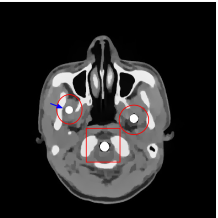

The proposed re-weighted JSR model requires a pre-estimation of the metal trace and weights in projection domain. They can be obtained fairly easily from a roughly reconstructed CT image using a simple reconstruction model. In this paper, we use the tight wavelet frame based analysis model [8]. This subsection describes the details on how metal trace and weights are computed using the NURBS-based cardiac-torso(NCAT) phantom [45]. Two metal components are implanted in the NCAT phantom as shown in Figure 1(a) and the simulated projection data is obtained from a multi-chromatic X-ray source. Details on the settings of the imaging system are postponed to Section 4.1.1.

The optimization problem (2.12) can be solved by the split Bregman algorithm [29, 8] efficiently, which is also equivalent to the alternating direction method of multipliers (ADMM) [24, 26, 28]. The reconstructed phantom image by model (2.12), denoted by , is shown in Figure 1(b). Metal location in image domain can be robustly estimated by the summation of the high frequency wavelet frame coefficients (Figure 1(c)) followed by a simple thresholding. Then, the index of the metal trace in Radon domain, denoted by , can be identified by the projection of the indicator function associated to the metal location (Figure 1(d)).

The NCAT phantom (shown in Figure 1(a)) and the cerebral phantom111http://see.xidian.edu.cn/vipsl/database_CTMR.html (shown in Figure 8(a)) are chosen as image phantoms. For the NCAT phantom, it has pixels. Two metal components (Titanium) are implanted in the image, which is shown in Figure 1(a) with red curves labeling the locations of the metals. For the cerebral phantom, it has pixels and three metal components (Titanium) are implanted. Both of the phantoms contain three major components, i.e. soft tissue, bone and metal components, and their linear attenuation coefficients can be found in [30].

Figure 7(a) shows that the reconstructed NCAT phantom from FBP has severe metal artifacts and is noisy. The reconstructed image from the unweighted JSR model (3.2) shown in Figure 7(b) has a better visual effect with noticeably less noise and metal artifacts. Sharp edges are also well preserved except for the blurry effects in the region surrounding the metals. The reconstructed image from NMAR shown in Figure 7(c) also has most of the metal artifacts suppressed and the regions surrounding the metals are much less blurry than the unweighted JSR. However, the unweighted JSR does a better job than NMAR in suppressing noise and preserving sharp image features away from the metals. TV-FADM is able to reconstruct images with minimum metal artifacts and noise, as shown in Figure 7(d). However, the metal components are fused with nearby structures which is highlighted by the red arrow. The reconstructed image from proposed re-weighted JSR model has the best overall quality with rather minor metal artifacts.

Figure 8 shows the reconstructed cerebral phantom from different methods. We highlight some regions with more distinct differences with red contours. Since the cerebral phantom contains more textures, it is more challenging than the NCAT phantom. The pros and cons of these methods are mostly the same as the previous example. However, we note that the reconstructed image from TV-FADM shown in Figure 8(e) has severe artifact, which is due to the well-known staircase artifact of TV regularization. We found that TV-FADM is relatively sensitive to the choice of its parameters. It is not easy to balance between sharpness of image features and metal artifacts reduction. The soft tissue around metal components is also not well preserved by the NMAR method as indicated by the blue arrow in Figure 8(d). Furthermore, the circled areas in Figure 8(d) show that there are still some artifacts around the metal. Same as the NCAT phantom, the proposed re-weighted JSR model has the best overall performance. Notice that the intensity of metals in Figure 8(d) and 8(f) seems lower than the rest of the reconstructed images. This is because we set the intensity of the metal components in the segmentation with the same mean value as that of bones. Increasing the value of metal components of can increase the intensity of metals in the reconstructed images, whereas it also introduces more artifacts around the metals.

Figure 11 shows the images reconstructed using FBP, the analysis model (2.12), the inpainting model (2.13) and the segmented image from the image obtained by (2.14). The reference image without metal implants are shown in Figure 11(a). All the images in this subsection are displayed within the grayscale interval . The segmented image shown in Figure 11(e) is used to estimate the weights needed in NMAR and the re-weighted JSR model.

Figure 12 shows a comparison between the reconstructed image from NMAR and the unweighted JSR model. Figure 13 shows a comparison between the reconstructed images from TV-FADM and the proposed re-weighted JSR model. Zoom-in views are provided in both Figure 12 and Figure 13 for a better visual assessment. As one can see that the reconstructed images from the unweighted JSR model and TV-FADM are less noisy than NMAR as indicated by the blue ellipse curve, whereas NMAR does a better job in preserving image features and suppressing metal artifacts. However, there are also new artifacts around the metal on the right as shown in Figure 12(d). The proposed re-weighted JSR model has best overall performance in terms of feature preservation, noise and metal artifact reduction.